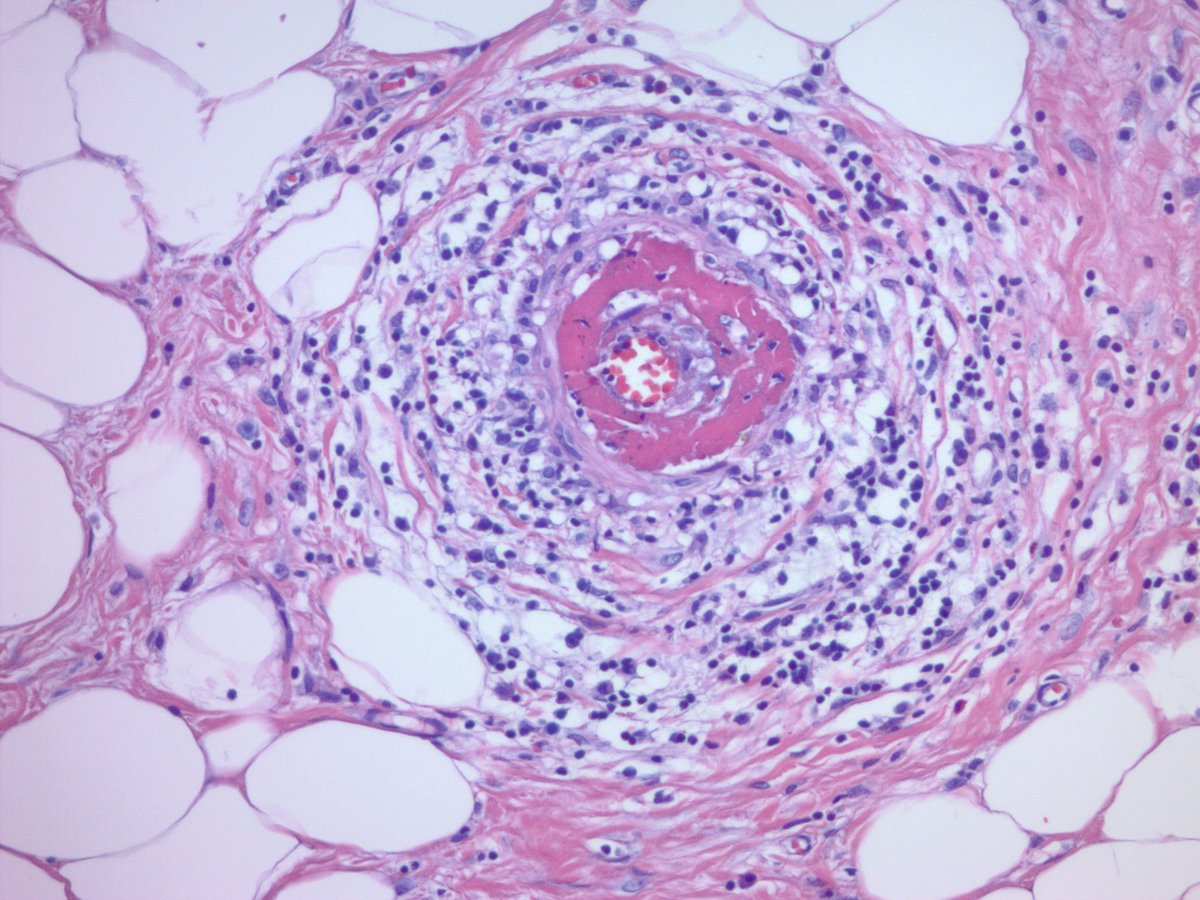

Appendix with lupus vasculitis. Appendectomy for presumed appendicitis. No acute appendicitis seen. Vessels within and outside of the appendix showed these changes with focal fibrinoid necrosis. Clinically and serologically active SLE. #GIpath #pathology

jake_bledsoe's tweet image. Appendix with lupus vasculitis. Appendectomy for presumed appendicitis. No acute appendicitis seen. Vessels within and outside of the appendix showed these changes with focal fibrinoid necrosis. Clinically and serologically active SLE. #GIpath #pathology